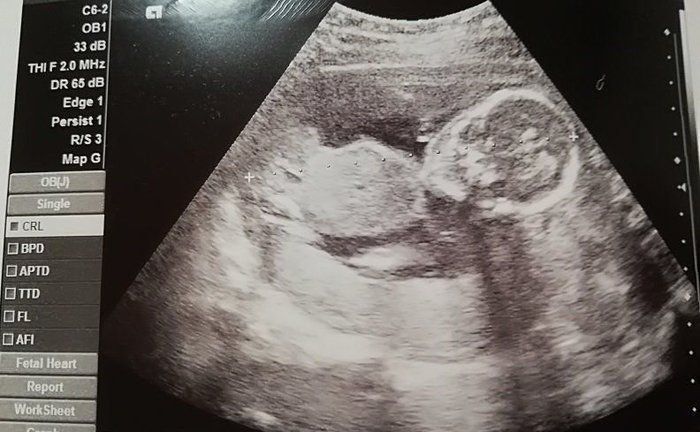

犬飼ねこさんの妊娠18週目のエコー写真

手の指がはっきりと見えます。